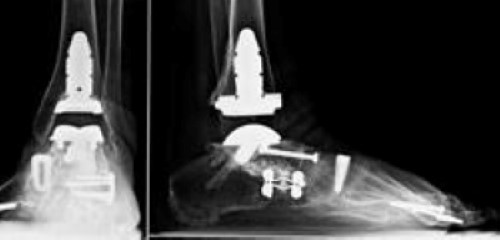

Ankle

Ankle fusion and total ankle replacement are the two primary surgical options for treating RA of the ankle. Both treatment options can be successful in minimizing the pain and discomfort in the ankle. The appropriate surgery is based on multiple factors and is individualized for every patient.

Ankle replacement may be right for you if you have:

- Severe involvement of other joints around the heel — meaning those joints are also severely affected by RA

- Previously undergone a fusion on the other leg

- Fusions within the same foot

Newer generation ankle replacement implants have shown promising early results. Ankle replacement implants have not yet been shown to be as long-lasting as those for the hip or knee, however, because the newer generation of implants have not been available long enough to determine how long they will last.

After ankle fusion, there is a loss of the up and down motion of the ankle. The up and down motion is transferred to the joints near the ankle. This creates a potential for pain in those joints, and possibly arthritis.

Patients are able to walk in shoes on flat, level ground without much difficulty after ankle fusion, despite the loss of ankle motion. The joints in the foot next to the ankle joint allow for motion similar to the ankle joint; this help patients with fused ankle joints walk more normally.

Ankle replacement has become a more viable option as newer generation of ankle implants have had greater success. Joint replacements in other parts of the foot have not been successful and may require fusions for pain relief and stability. Often, an ankle replacement is performed after other areas of the foot have been fused and are therefore able to provide appropriate support for the ankle replacement.